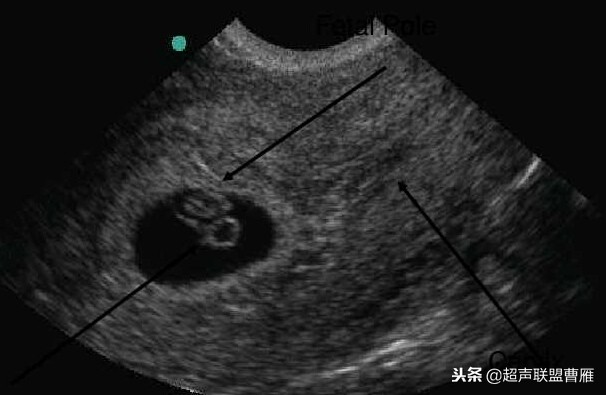

孕7周左右(胚芽11mm 卵黄囊)

卵黄囊 羊膜囊 小胎儿雏形 (卵黄囊直径8.5mm)